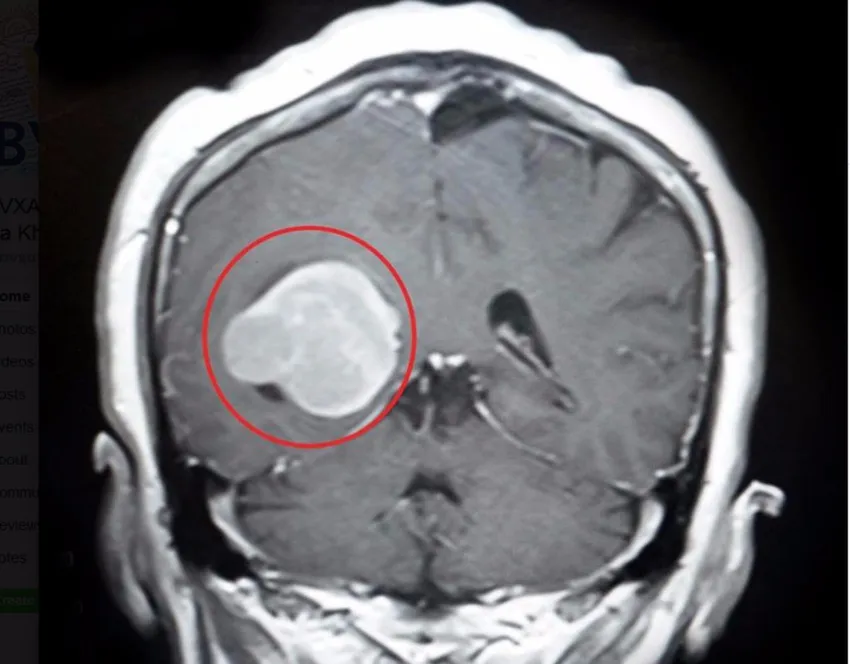

Khối u màng não to như trứng gà. Ảnh: LÊ PHỤNG

Các bác sĩ (BS) chuyên khoa Ngoại thần kinh thực hiện chẩn đoán và xác định bà L. có khối u não nằm trong não thất phải, ở vị trí hiếm gặp liên quan tới vùng chức năng vận động và thị giác.

Các BS nhận định một khi u màng não ngày càng to sẽ lấn đè vùng chức năng mô não, làm tăng áp lực nội sọ khiến tình trạng đau đầu ngày càng nhiều. Chưa hết, bà L. có nguy cơ mờ mắt, tay chân yếu dần, rối loạn cảm giác, mất cảm giác da, liệt nửa người. Nếu nặng hơn bà L. sẽ lơ mơ, hôn mê, thậm chí tử vong.